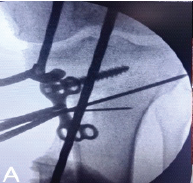

Most of the participants were right-hand dominant (97.7%, n = 774), whereas a small percentage (2.3%, n = 18) were left-hand dominant, highlighting demographic variations among the surveyed population. Professionally, a significant proportion of respondents (84.1%, n = 666) were early-career surgeons with <5 years of practice, while 11.3% (n = 90) were established professionals with over a decade of experience. Regarding workplace settings, teaching institutions employed the majority (73.8%, n = 585), followed by non-teaching government facilities (19.4%, n = 153) and private institutions (6.8%, n = 54), illustrating a diverse distribution of practice environments. The survey represented a broad range of orthopedic subspecialties, with 33% (n = 261) of surgeons specializing in a single domain and others working across multiple subspecialties, including trauma surgery, arthroplasty, spine surgery, arthroscopy, pediatric orthopedics, orthopedic oncology, and hand surgery. The weekly surgical workload of respondents varied significantly, with 39.8% (n = 315) performing limited surgeries (<12 h/week) and 21.6% (n = 171) engaged in high-volume procedures (>36 h/week). Most surgeons (83%, n = 657) operated exclusively in a standing position, whereas a smaller proportion (14.8%) alternated between sitting and standing during surgeries. In addition, routine use of lead aprons during procedures was reported by 70.5% (n = 558), emphasizing radiation safety as a noteworthy concern among the respondents. The distribution of MSOI is presented in Fig. 1.

Figure 1: Regional distribution of musculoskeletal occupational injury among the survey respondents.